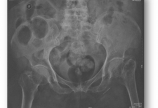

病情概述: 李某,女,汉族,81岁,某厂退休工人,75kg。走平路时跌倒致左髋部疼痛、活动受限10天。患者10天前散步时,因躲闪对面行人不慎跌倒致左侧肢体着地,当即感到左髋部疼痛、站立和行走困难。摔倒时无昏迷、恶心呕吐、胸腹腰部疼痛二便失禁等。卧床休息数日后,疼… [详情]